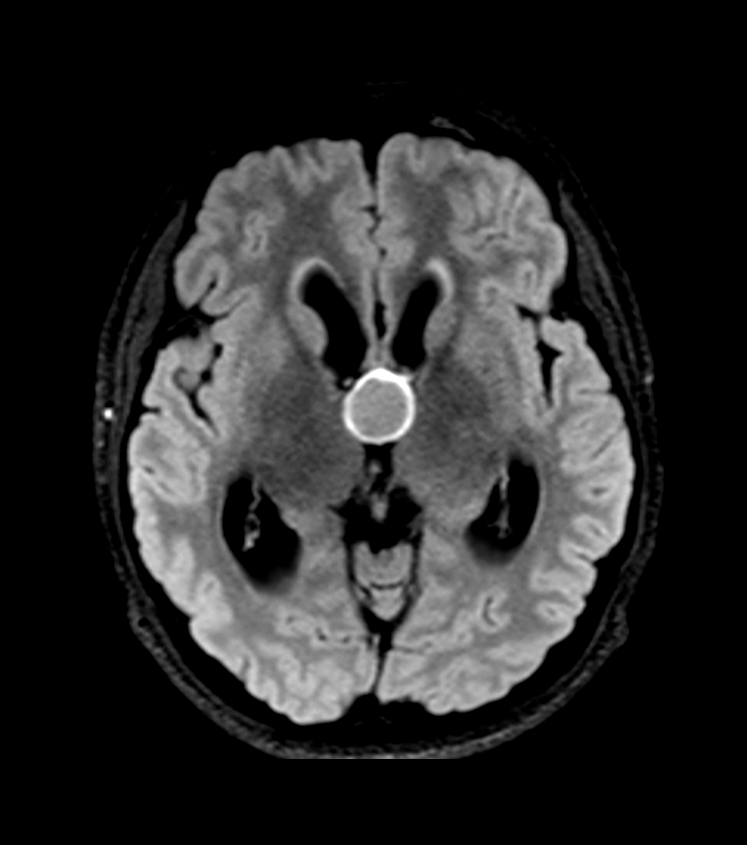

- CT findings:

- Hyperdense, round lesion in the anterior third ventricle

- Usually measures 3-15 mm in diameter

- May demonstrate rim calcification

- 55-year-old patient presented with bladder dysfunction and unsteadiness.

- CT showed a 7 mm hyperdense lesion filling the foramen of Monro and marked enlargement of the ventricles.

- There was very little periventricular oedeam, and so the appearances suggest chronic, compensated, ventriculomeagly (rather than acute hydrocephalus).